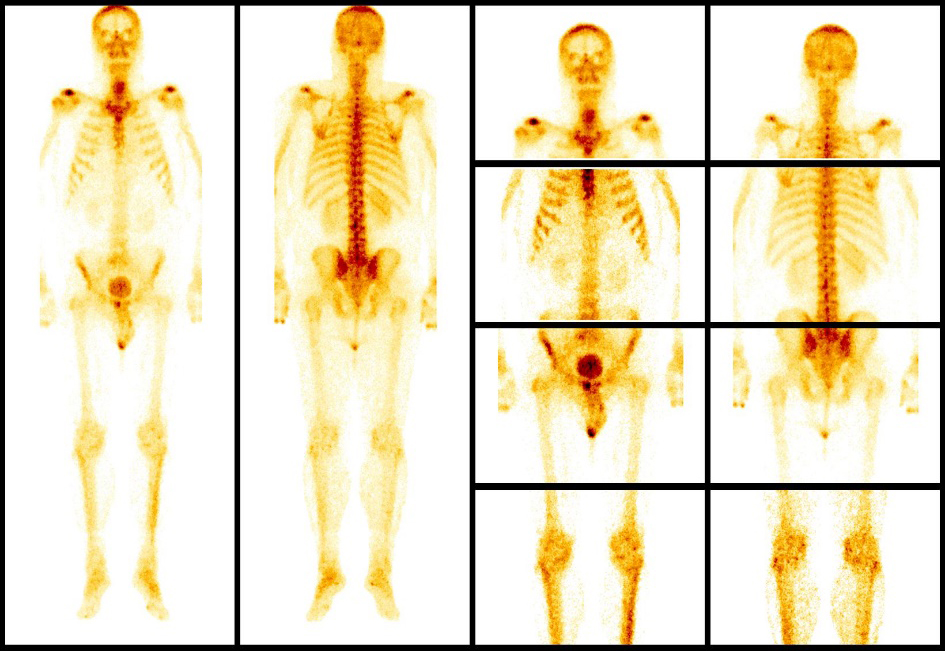

- Остеосцинтиграфия. Исследование костей организма с контрастным веществом, которое накапливается в костной ткани и при исследовании всего скелета подсвечивает очаги опухоли.